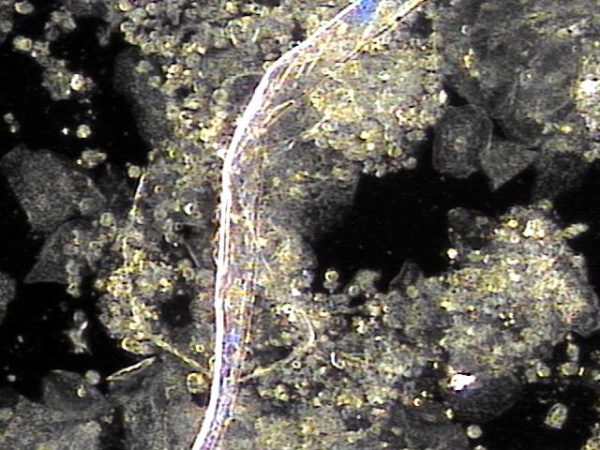

주2회 전립선의 표적 치료후 치료된 상피 세포 덩어리의 현미경학적 자료입니다.

"This is the microscopic data of the epithelial cell clusters treated after targeted prostate therapy twice a week."